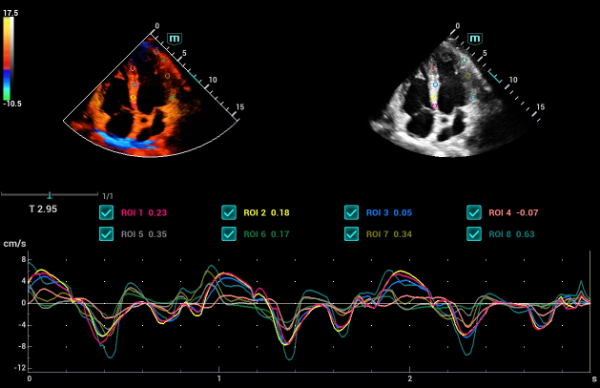

- TDI – Tissue Doppler Imaging

- TDI Quantification Analysis Software

- Tissue Tracking with Quantitative Analysis